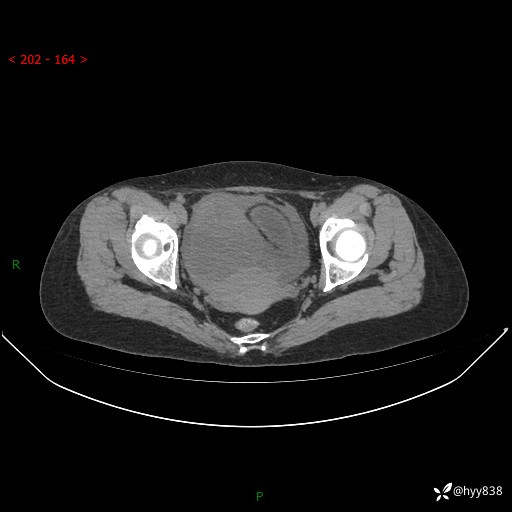

老年女性,尿频2月。超声发现盆腔囊实性占位,CT能否明确诊断---结果公布

现病史:患者绝经3-4年,期间无阴道出血及排液。患者近2月感尿频,自行口服中药治疗,症状无明显缓解。2024-4-25日于我院门诊就诊,行阴道彩超示:子宫肌瘤(大小约12*10mm,后壁),子宫右前方囊实性占位性病变(大小约126*82mm肿块声像,边界尚清,以无回声为主,可见范围约84*27mm稍高回声),内膜3mm。建议手术治疗。门诊以“卵巢囊肿”收入院。 病程中精神、食欲、睡眠可,大小便正常,体重体力无明显变化。

增强